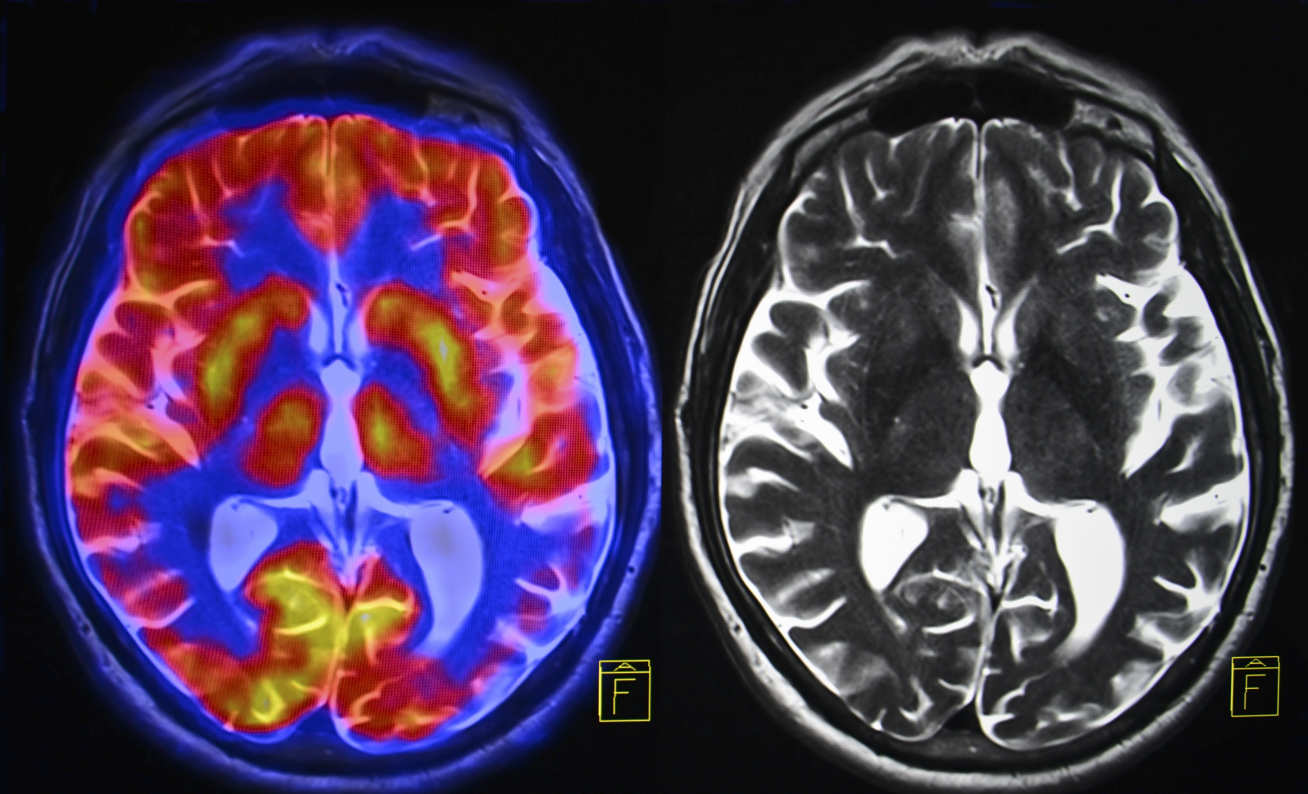

Scientists are creating an ‘atlas’ of the brain at different stages of Alzheimer’s disease